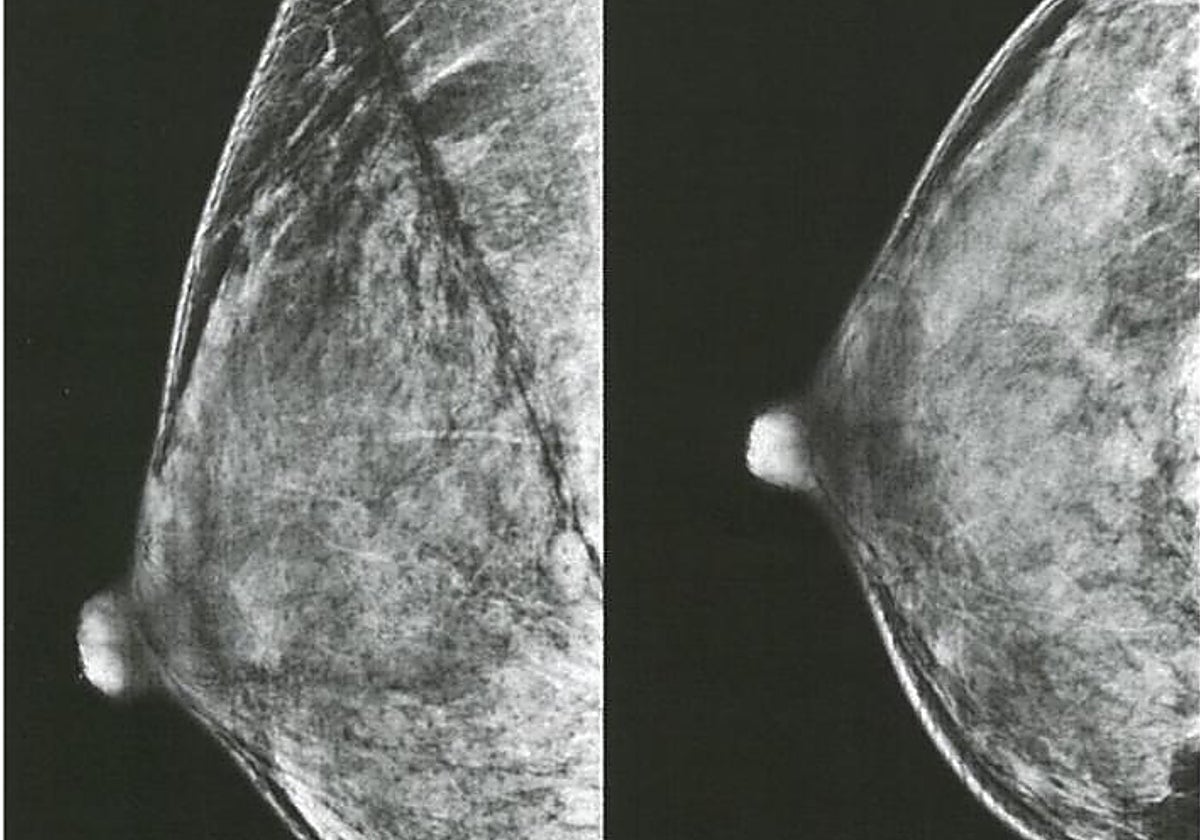

EE.UU. y Europa cambian sus recomendaciones para la primera mamografía: ¿Cuándo hay que hacerla entonces?

Nuria Ramírez de CastroLas nuevas guías estadounidenses aconsejan empezar a los 40 años en lugar de a los 50. El plan europeo del cáncer pide no solo adelantar sino extender el chequeo hasta los 75 años